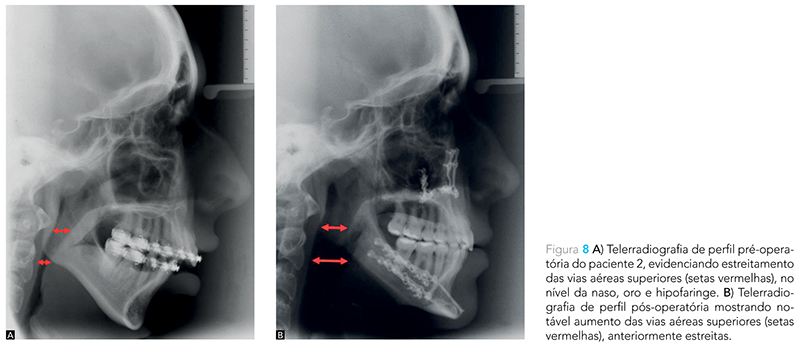

A cirurgia ortognática por meio da osteotomia sagital bilateral do ramo mandibular (OSBRM) permite o avanço do processo dentoalveolar juntamente com o alongamento dos músculos digástricos (ventre anterior); milo-hióideo, genioglosso e do gênio-hióideo. Dessa forma, a base da língula é deslocada para a frente e para cima, promovendo o aumento do espaço aéreo posterior e criando espaço para o reposicionamento lingual. Nesse contexto, o avanço maxilar traciona o palato mole e o músculo palatoglosso para anterior, aumentando a área retro-palatal e o suporte da língua10 (Fig. 5 e 7). Além disso, a genioplastia de avanço também permite o aumento do espaço aéreo posterior pela reposição anterior da língua10 (Fig. 6, 8 e 9).